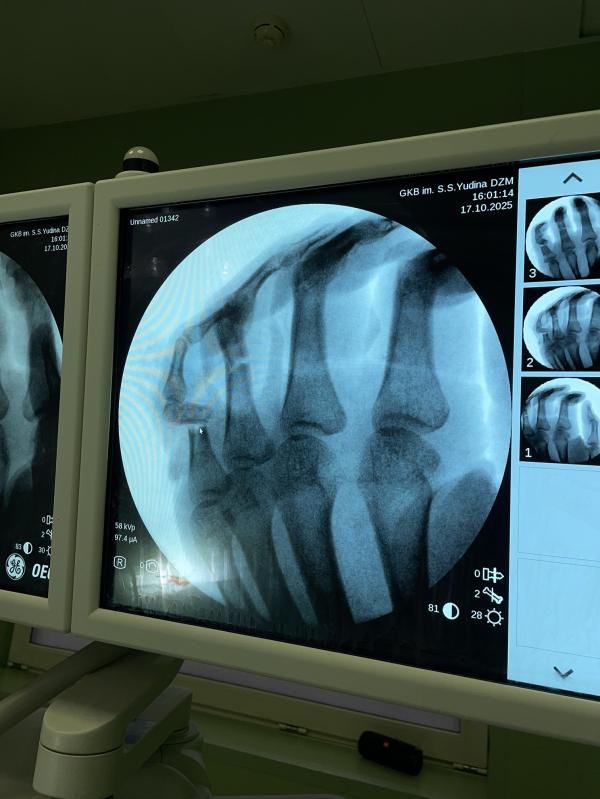

Так жалко, поступают молодые парни (узбеки, таджики) с производственными травмами и скрывают правду , где и как поранились , ведь это и может поменять суть . Прикрывают своих работодателей , думая что им возместят весь ущерб , но из практики ни хрена .